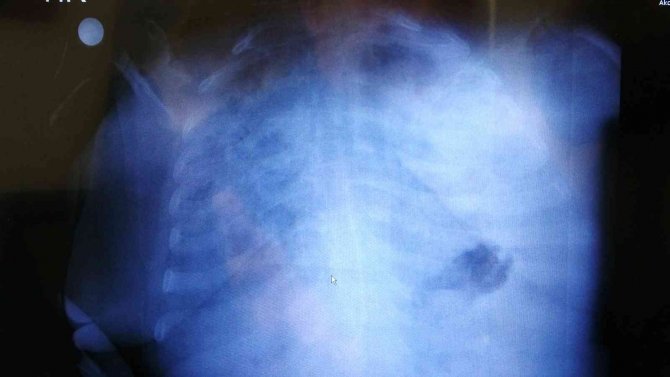

"Geldiğinde hiç akciğeri kalmamıştı"

Aşının yan etkilerinden korkarak aşı tereddüdü yaşayan 48 yaşındaki Şule Karabulut'un akciğerlerini inceleyen Özkaya," Hastalanmadığı için 2 sene şanslıymış. Bu dalgada hastalandığı için ciddi akciğer tutulumu ile geldi. Neredeyse hemen hemen hiç akciğeri kalmamıştı. Yoğun bakımda solunum desteği ile takip ettik bu hastayı. 48 yaşında genç hastayı az kalsın kaybediyorduk. Yoğun bakımda günlerce yatmak zorunda kaldı. Genç olduğu için ve erken müdahale ettiğimiz için akciğeri düzeldi. Taburcu olacak" ifadelerini kullandı.